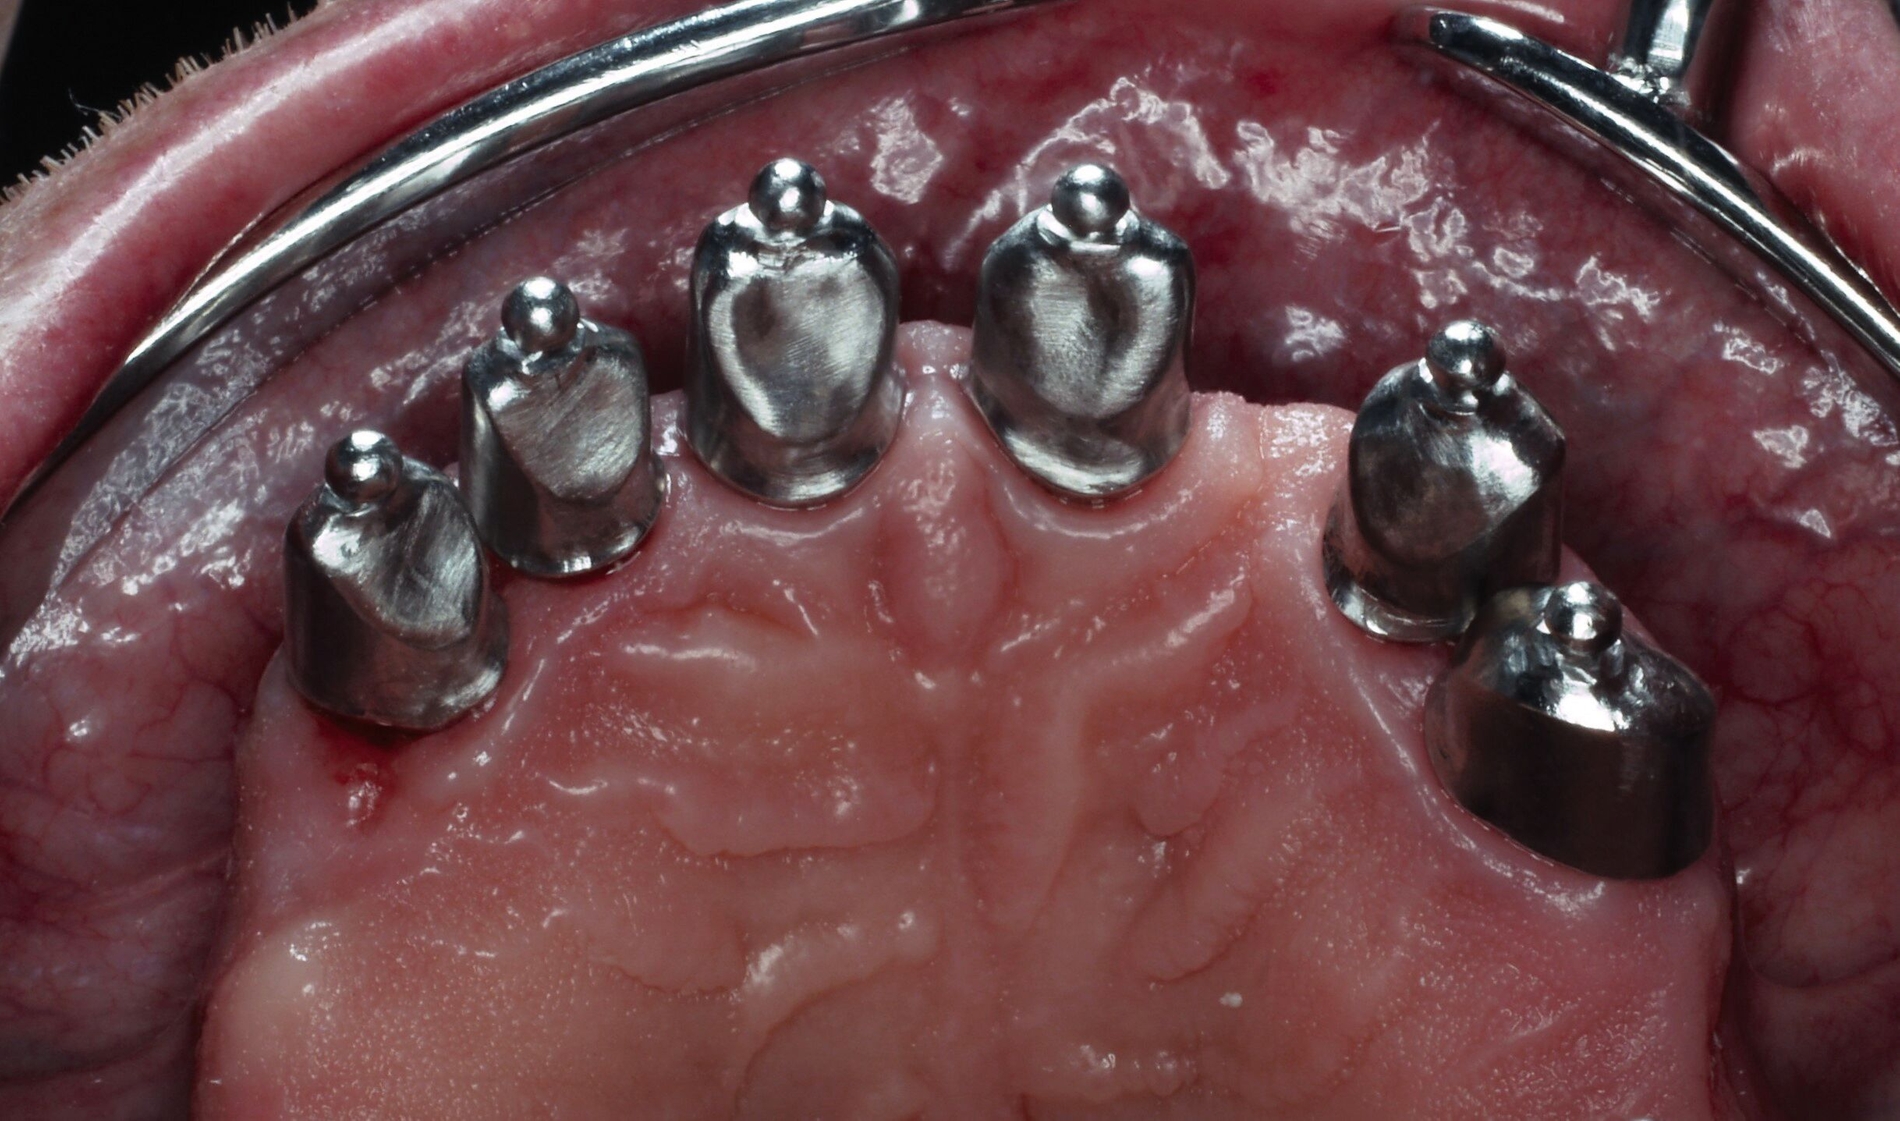

Die Stümpfe wurden folglich zur Aufnahme von Teleskopkronen präpariert und mittels Doppel-Fadentechnik für die konventionelle Abformung mit dem Polyether vorbereitet. Nachdem das zahntechnische Labor die NEM-Primärteleskope hergestellt hatte, wurden sie am Patienten anprobiert und mit einem Tropfen provisorischen Zements auf den Stümpfen fixiert (Abbildung 5a), um sie anschließend in der Fixationsabformung mit abzuformen (Abbildung 5b).

Auf dem Meistermodell wurde vom Labor nun der Wachswall zwecks Kieferrelationsbestimmung hergestellt. Nach Überprüfung der Ruheschwebelage von 2 mm wurde der Wachswall verschlüsselt. Bei der Gesamtanprobe konnte neben der Kontrolle der statischen/dynamischen Okklusion und der Ästhetik das spannungsfreie Gleiten des Prothesengerüsts in die Primärteleskope überprüft werden.